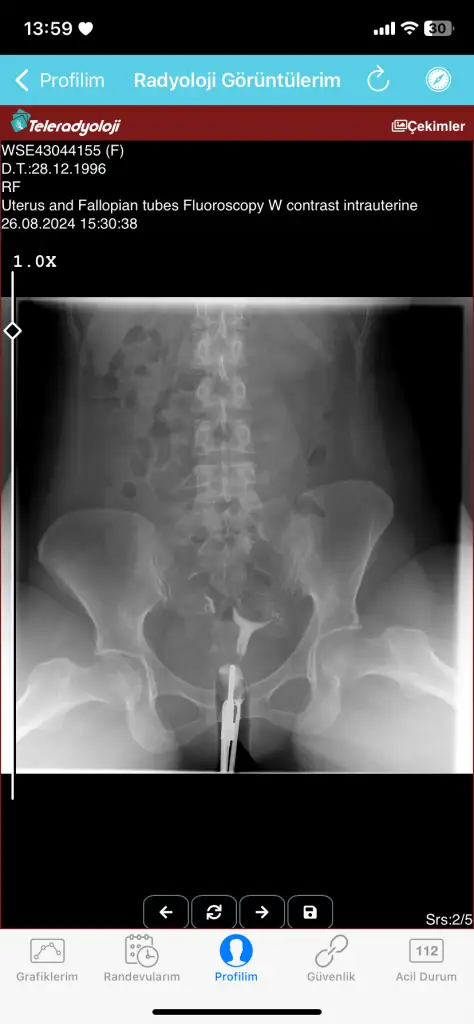

Atabilirmisiniz resminiİşte ben gebe kaldım fakat dış gebelik oldu bundan ötürü mü oldu dedim doktoruma hayır dedi rahmin yeteri alan var dedi hatta varsa resim atayım size kendikimin

Ama sizin rahimde V seklinde degil ki kenarlardan basık bu engelmi acaba ya hic bilmiyorum

İşte evet aslında şöyle çok az normal rahimli kadın varmış doktorum öyle söyledi şimdi ben rahim şeklim bu haldeyken gebe kaldım demek gebeliğime engel değilmiş onu gördük fakat daha düşük vs olmadı umarım olmaz da doktorum ben bunun çok çok daha kötülerini gördüm dedi onlar bile 38,39 haftalara kadar geldiler dedi artık doktoruma güvendim rahim esnek ya bebek için bu görüntüde yeteri alan var dedi umarım dediği gibide olur aslında sizin ikinci resim de artık düzeltebileceği kadar düzeltmiş aslı v değil ters armut üçgen şeklinde olması gerek zaten bebek için yeterli alan açıyorlar amaç bu ameliyatın aslında o şekilde bile öyle çok sağlıklı doğuran var ki işte nasip mesele zahide küçük var doktor Cem çelikle çok canlı yayını oluyor instagramda son postuna bakın zahide hanımın rahimde perde olan kadın gebe kalmış ve bebeği ve kesesi gayet sağlıklı durumda bakın isterseniz yani rahim esnek olduğundan düzelme şansıda oluyorAma sizin rahimde V seklinde degil ki kenarlardan basık bu engelmi acaba ya hic bilmiyorum

Kenarlardan değil üstten basıkAma sizin rahimde V seklinde degil ki kenarlardan basık bu engelmi acaba ya hic bilmiyorum

Benim ki tam t değil canım ben gebede kaldım doktor ameliyatlık değil dedi yeteri alan var dedi sağlıksız gebelik oldu benim kiBenim arkadaşım var rahmi egri gebe kalamiyodu tup bebekle oldu gayette saglikli gecti hamileligi. Ben kendim hic hamile kalmamistim bence bendeki bu T rahim kesinlikle gebelige engeldi ama sizin durumunuz farkli tabikide. Siz hamilelikmi düşünüyorsunuz